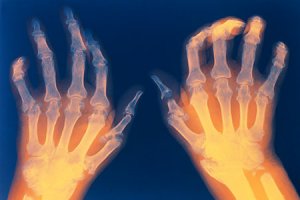

Более 30 млн человек во всем мире ежедневно принимают нестероидные противовоспалительные препараты (НПВП) для лечения боли и воспаления [40]. Среди потенциально опасных побочных эффектов НПВП наибольшее значение имеют желудочно-кишечные (ЖК), сердечно-сосудистые (СС) и почечные. Если проблема ЖК токсичности в значительной мере была решена путем внедрения нового класса препаратов – специфических ингибиторов циклооксигеназы 2-го типа (ЦОГ-2)*, то ситуация с другими побочными эффектами существенно не улучшилась.

О.Б. ЯременкоВ руководствах по лечению боли и артритов/артрозов Американской ассоциации боли (APS, 2002), Американской коллегии ревматологов (ACR, 2000) и Европейской противоревматической лиги (EULAR, 2003) НПВП и специфические ингибиторы ЦОГ-2 занимают ведущие позиции и рекомендации по их назначению базируются именно на соображениях ЖК безопасности. Все три профессиональные организации рекомендуют для лечения слабой и умеренной суставной боли парацетамол, исходя из его низкой стоимости и относительно благоприятного профиля побочных эффектов. Согласно рекомендациям APS, для купирования умеренной и сильной боли при ревматоидном артрите и остеоартрозе предпочтительны специфические ингибиторы ЦОГ-2. Использование неселективных НПВП обосновано только в тех случаях, когда отсутствует адекватный ответ на ингибиторы ЦОГ-2 и нет повышенного риска НПВП-индуцированных ЖК побочных эффектов. EULAR рекомендует применение неселективных НПВП совместно с гастропротекторами. Ингибиторам ЦОГ-2 отдается предпочтение при лечении больных с повышенным ЖК риском. ACR констатирует целесообразность комбинации на первом этапе нефармакологических воздействий с парацетамолом, у лиц с недостаточным эффектом могут быть использованы НПВП. Если пациент имеет повышенный риск ЖК осложнений, показаны специфические ингибиторы ЦОГ-2. В качестве альтернативы можно применять НПВП с гастропротекторами.